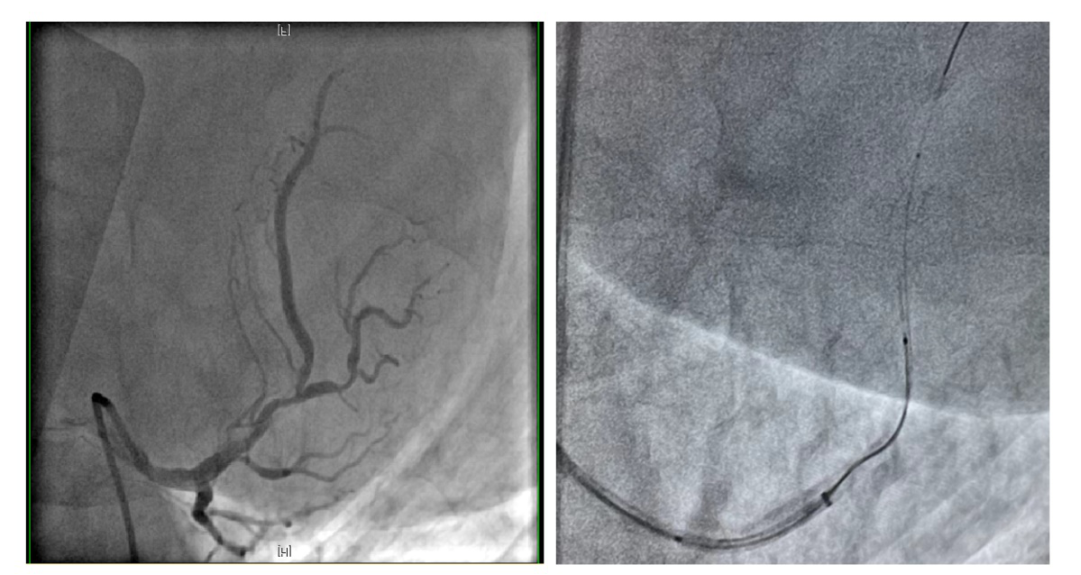

患者为一位65岁的男性冠心病患者,先期因急性心肌梗死行左回旋支介入治疗,此次造影显示,前降支近中段有重度狭窄伴有严重钙化及血管迂曲等,需要进一步介入干预。经讨论,心脏内科介入团队制订了细致的手术计划:首先通过OCT与冠脉造影融合技术,进一步准确评估冠脉钙化范围及深度,必要时采用Shockwave冲击波球囊技术方案,精确冲击冠状动脉内膜或中膜下钙化病灶后,再次使用OCT评估治疗效果并精准定位释放支架。

LAD造影提示近中段钙化严重(左)导管支持下通过OCT导管(右)

OCT-冠脉造影融合技术评价钙化病变并实时定位

经过充分的术前准备,6月21日,手术正式开始。术中,如术前预判,OCT检查提示患者前降支近中段多处偏心钙化及环形钙化,钙化厚度1.2mm以上,钙化严重导致多种介入器械难以通过,旋磨或激光等处理方法也难以实施,因此,在OCT及冠脉造影融合技术精准指导下,启动Shockwave冲击波球囊技术方案。